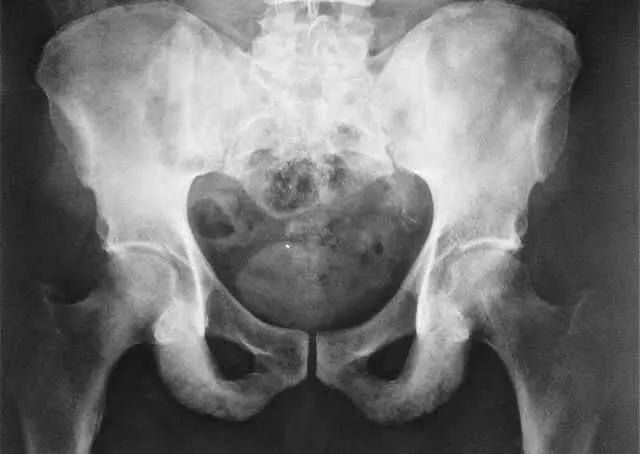

- Досить показовим є рентген при хворобі Бехтерєва.